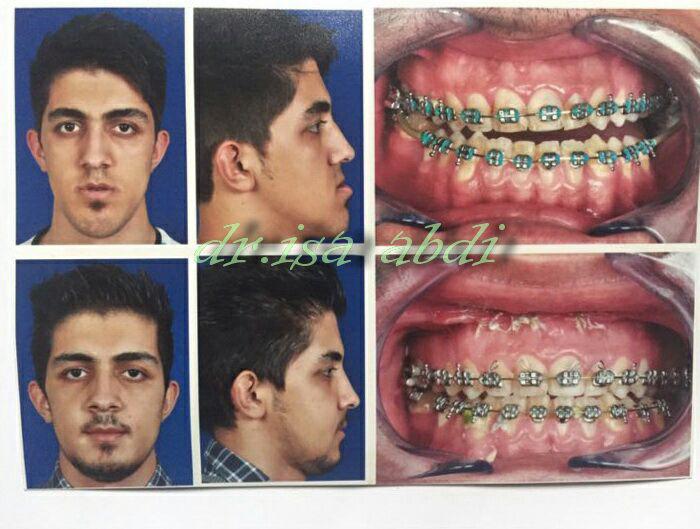

جراحی فک , پلاستیک , صورت وبینی

جراحی نواقص مادرزادی و اکتسابی

چه افرادی نیاز به جراحی فک دارند؟

به صورت مادرزادی در ناحیه فک مشکل دارند.

صورتشان از روبهرو و پهلو تقارن ندارد.

در جویدن و گاز زدن مشکل دارند.